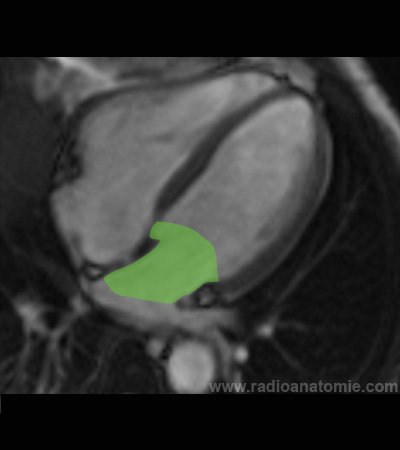

Radioanatomie et plans de coupe en IRM cardiaque

Oreillette droite

Oreillette gauche